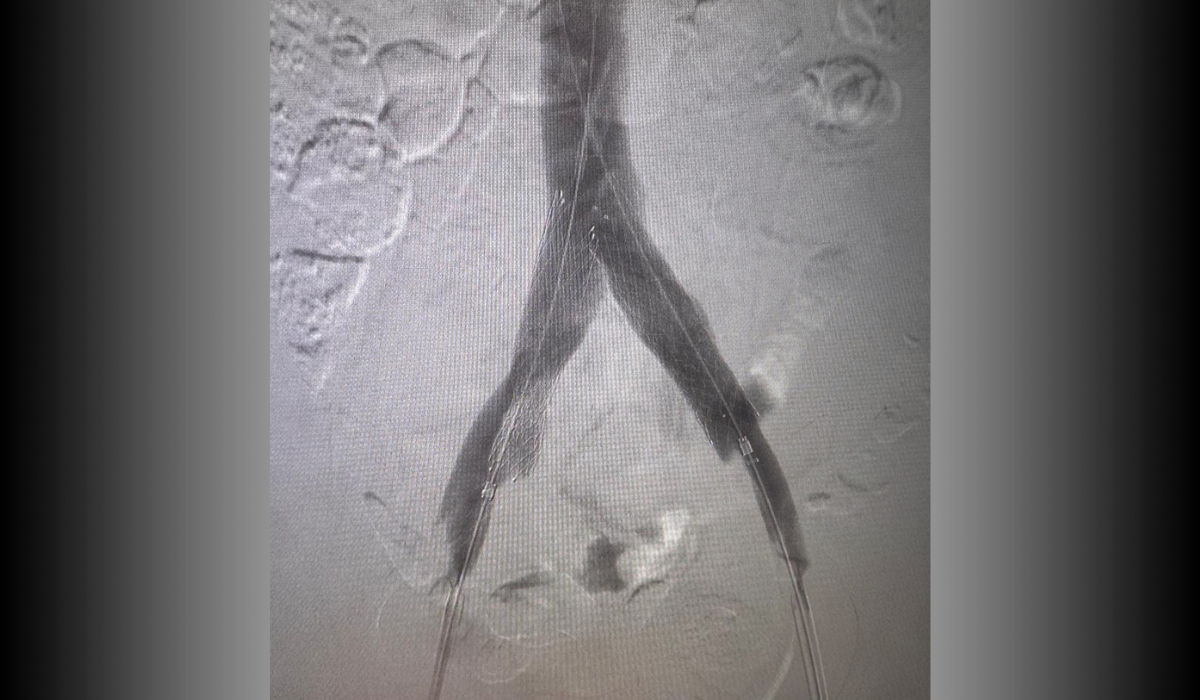

Después: Reconstrucción con stents

Después

Reconstrucción con stents. Flujo normalizado y resolución clínica.

Oclusión de ambas venas ilíacas/Sindrome de congestión pélvica